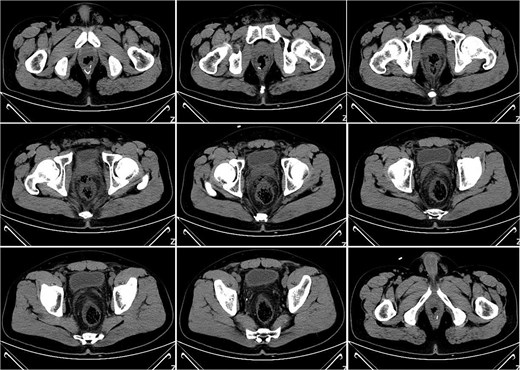

On postoperative Day 15, a complete blood count showed a white blood cell count of 9.12 × 109/l and a neutrophil percentage of 77.5%. Pelvic CT demonstrated rectal wall edema, anterior wall perforation, and partial absorption of the surrounding infection, indicating reduced infection severity compared to the previous scan on postoperative Day 10 (Fig. 3). Given the patient’s satisfactory response to antibiotic therapy and absence of ongoing infection signs, intravenous antibiotic treatment was discontinued.